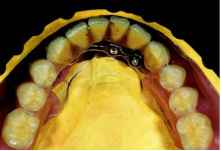

не челюсти, что еще больше затрудняет восстановление оптимальной анатомической формы ее язычной поверхности. Диагностическая постановка зубов На первом этапе с помощью искусственных зубов и соответствующего полимерного основания осуществляется изготовление первой диагностической модели будущей реставрации и ее предварительная примерка. При этом в центральной части модели необходимо сформировать достаточно широкую полость, в которой должны разместиться не только абат-менты всех четырех имплантатов, но и фиксирующие винты! Затем на основании результатов предварительной примерки проводится окончательная коррекция структуры диагностической модели, после чего можно приступать к моделированию внешней конструкции новой реставрации. Первичная конструкция На этом этапе осуществляется со-шлифовывание центральной части язычной стенки модели, удаление излишков полимерного материала, а в случае необходимости и дополнительное препарирование искусственных зубов, расположенных в непосредственной близости от абат-ментов имплантатов, и повторная фиксация диагностической модели реставрации на рабочей модели нижней челюсти. Только после этого мы впервые можем в полной мере оценить все особенности взаимного расположения имплантатов и зубного ряда внешней конструкции новой реставрации (рис. 5 и 6). Использование так называемых «кнопочных анкеров» в данном случае абсолютно нецелесообразно: матрицы таких анкеров имеют совершенно определенные и достаточно большие размеры (высота и диаметр), вследствие чего мне пришлось бы разместить их еще дальше в вентральном направлении, что, разумеется, не только не улучшило, а, напротив, еще больше усугубило и без того крайне сложную клиническую ситуацию. В конечном итоге я пришел к выводу, что наиболее оптимальным вариантом выхода из сложившейся ситуации является изготовление соединительной балки, которая должна располагаться как можно дальше в вестибулярном направлении, а также быть очень неоднородной по высоте. При этом максимально низкой она должна быть в наиболее критичной области,

то есть вблизи зуба 43. Для выполнения этого условия непосредственно перед фрезерованием абатмента имплантата зуба 43 его верхнюю ок-клюзионную часть нужно аккуратно сошлифовать вплоть до минимально допустимого уровня. При этом необходимо тщательно следить за тем, чтобы после завершения этой операции его верхний край располагался чуть выше головки постоянного фиксирующего винта. Фрезерование восковой модели соединительной балки Формирование структуры соединительной балки осуществляется в процессе нанесения воска и его последующего фрезерования. Непосредственно перед этим поверхность оригинальных способных к литью элементов первичной конструкции необходимо покрыть слоем материала Pattern Resin, заполимеризовать его, а затем обязательно с использованием стереомикроскопа сошли-фовать до минимально возможной толщины. При этом особое внимание необходимо обращать на точность и качество формирования структуры границ перехода и внешних кромок. Шлифование полимерных капп следует проводить только после фиксации специальных вспомогательных приспособлений, что позволяет полностью исключить возможность случайного повреждения абатментов, поскольку даже легкое соприкосновение рабочей части абразивного инструмента с базовой поверхностью абатментов, которые находятся в непосредственном контакте с имплантатами, делает их абсолютно непригодными для дальнейшего использования. Для соединения полимерных капп друг с другом я обычно использую стандартные тонкие восковые пластины. Затем, на это «основание» наносится равномерный слой фрезеровочного воска, который должен покрывать не только восковые пластины, но и всю поверхность полимерных капп, после чего с помощью специальных фрез для воска осуществляется предварительное фрезерование модели соединительной балки. Контроль качества. Присоединение литников На следующем этапе проводится формирование литниковой системы, удаление фиксирующих винтов, снятие восковой модели и удаление дес-невой маски. После этого уже без использования фиксирующих винтов осуществляется предварительная примерка восковой соединительной балки на рабочей модели без десневой маски, что значительно облегчает контроль точности ее фиксации, наличия пассивной посадки и отсутствия краевых зазоров (рис. 7). Если качество фиксации восковой модели не соответствует хотя бы одному из вышеперечисленных требований, то ее нужно еще раз разделить на несколько деталей и снова соединить их в единую конструкцию и, в случае необходимости, повторять эту процедуру вплоть до достижения необходимого результата. Дополнительную проверку точности фиксации восковой модели и наличия или отсутствия краевых зазоров можно провести в процессе контрольного завинчивания каждого фиксирующего винта по отдельности. Внешний вид готовой восковой модели соединительнойбалки наглядно продемонстрирован на рисунке 8. При более подробном анализе ее структуры особое внимание следует обратить на прецизионную точность фиксации восковой соединительной балки (рис. 9 и 10), более чем успешную компенсацию различной высоты опорных имплантатов (рис. 11), а также минимальную высоту и толщину язычной стенки балки в области зуба 43 (рис. 12). Литье В своей практике для изготовления литых деталей любых стоматологических реставраций я обычно использую так называемую «ускоренную» технологию формования. При этом, если в состав восковой модели входят оригинальные способные к литью металлические детали, то для повышения качества соединения формовочной массы с их поверхностью, особенно вблизи внешней кромки, и обеспечения высокого качества литья, температура предварительного прогрева формованной заготовки должна составлять примерно 700оС (конкретное значение зависит от типа формовочной массы). В отличие от некоторых своих коллег я до сих пор абсолютно убежден в том, что использование большего, чем это действительно необходимо, количества золотого сплава и формирование дополнительного резервуара для расплава позволяет значительно повысить качество центробежного литья (рис. 13). Ярким доказательством справедливости этого мнения является увеличенный снимок литой соединительной балки (рис. 14), на котором отчетливо видны немного выступающие над поверхностью абатментов, но, несмотря на это, абсолютно четкие и ровные границы переходов от оригинальных абатментов к поверхности золотого сплава без каких-либо пор или усадочных раковин. Фрезерование Благодаря наличию съемной дес-невой маски, фрезерование литой соединительной балки можно проводить непосредственно на рабочей модели. Я считаю, что нет никакой необходимости еще раз подробно описывать все особенности проведения этой чрезвычайно ответственной операции, поскольку в данном случае, впрочем, как и во всех предыдущих, она осуществлялась в точном соответствии с традиционной и широко известной технологией. Как уже было сказано выше, в своей практике для |